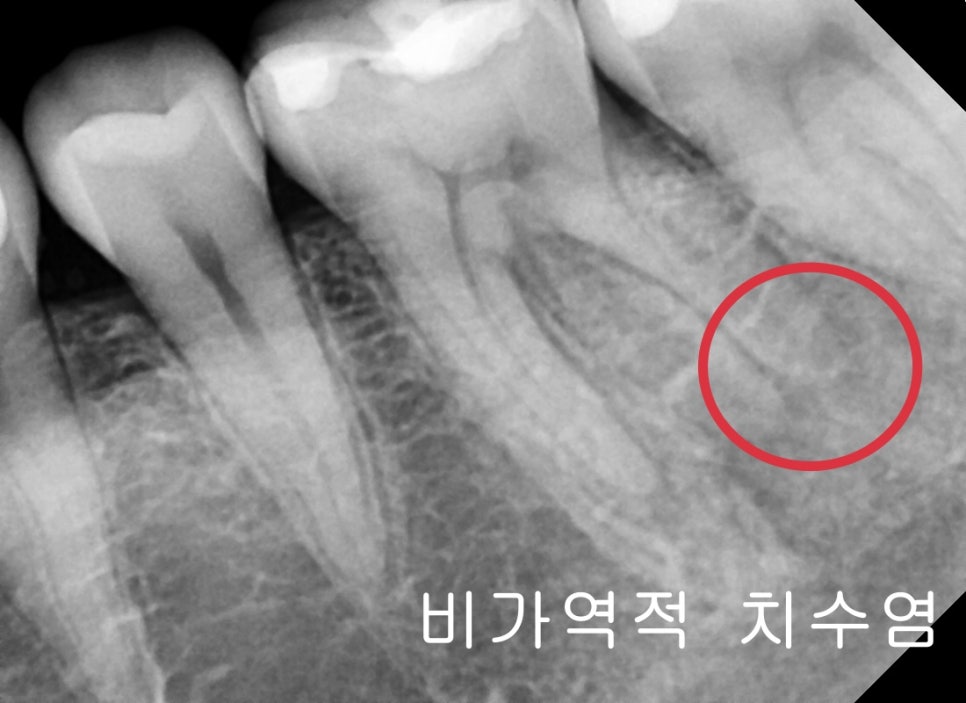

치아 내부 신경에 염증이 생기는 것을 치수염이라고 합니다

치수염에는 초기에는 회복이 가능한 가역적 치수염과

자연적 회복이 불가능한 비가역적 치수염으로 구분할 수 있습니다

비가역적 치수염은 이미 신경의 괴사로 인해 치아 내부의 가스로 인한

압력이 통증을 유발하는데 이 정도는 약으로는 조절이 잘 안됩니다.

환자분의 증상 자체가 비가역적 치수염으로 판단되어집니다.